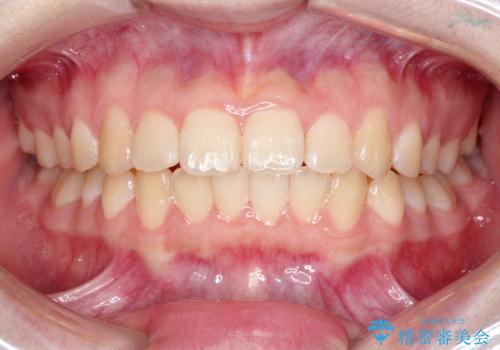

なるべく通院回数を減らして矯正したい インビザラインでのガタガタ矯正

- 1年2ヶ月

- 10-30回

- 上下の歯並びを治したいとのことで来院されました。

受験生ということもあり、なるべく通院回数を減らしての矯正を希望されたので、インビザラインで治療をすることにしました。

ワイヤー矯正が1か月に1回程度来院が必要なのと比較すると、2-3か月に1回の来院でもよいので(症例によります)、通院回数を減らすことができて、患者様の負担を減らすことができます。